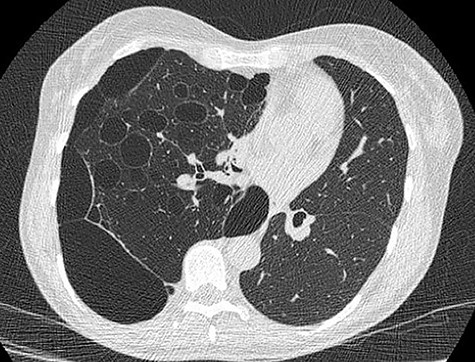

We present a 45 year-old lady who had initially been seen by the respiratory physicians following an admission with acute dyspnoea following influenza infection 1-year prior to her surgery. She had undergone CT scan for abnormal chest radiograph. She had previously worked as a cleaner and was an ex-smoker of 1.5 pack years with no previous asbestos exposure or underlying genetic disease such as tuberous sclerosis or alpha-1 antitrypsin deficiency. She had been followed up in the nodule clinic (a follow-up clinic run by respiratory physicians to monitor solitary pulmonary nodules) with a provisional diagnosis of chronic obstructive pulmonary disease. She had progressive dyspnoea and occasional lower respiratory tract infections treated with courses of antibiotics. Her co-morbidities included previous alcohol dependence and depression. Pre-operative pulmonary function tests demonstrated an FEV1 of 1.53 (53% of predicted), FVC of 2.52 (79% of predicted), diffusing capacity of lungs for carbon monoxide (DLCO) of 5.25 (62% of predicted) and 6 minute walking distance of 414 m. Initial CT imaging findings demonstrated severe, heterogenous right-sided bullous emphysematous changes with a basal predominance and multiple large bullae in the lower lobe (Fig. 1) and a benign inflammatory nodule, which was 7 mm in size in the right upper zone presumably right upper lobe. There was associated hyperinflation causing mediastinal shift to the left with complete right middle lobe collapse and marked compression of the right upper and middle lobes. Due to her increasing symptoms and progressive solitary nodule (Fig. 2) in the right upper zone she was referred for a surgical opinion. Pre-operative echocardiography did not demonstrate any right ventricular dilatation or impairment and no pulmonary hypertension. She was counselled regarding the progressive symptoms, lung function and risk of pneumothoraces and scheduled for right thoracotomy and lower lobectomy. Operative findings were that of large bullous disease affecting the right lower lobe (Fig. 3) with subtotal destruction of the lung parenchyma of the lower lobe. The nodule was present in the apical segment of the lower lobe instead of the upper lobe as expected. Right lower lobectomy was completed un-eventfully and the specimen was sent for histology. The upper and middle lobes were hypoplastic and the post lobectomy space management was a challenge. Post-operatively recovery was complicated by prolonged post-operative air leak managed conservatively and once this eventually settled, the patient was discharged following removal of the chest drain. Histopathological analysis of the right lower lobe specimen demonstrated several large thin-walled cysts with interstitial clusters of spindle cells bordering the cyst and immuno-histological markers (increased expression of VEGF-R3, Podoplanin, LYVE-1 and PROX-1) confirming a diagnosis of LAM. The patient was seen in the thoracic surgery follow-up clinic and a CT abdomen/pelvis was organized to rule out renal angiomyolipomas, associated with LAM in tuberous sclerosis. Referrals were made to the respiratory physicians and the National LAM centre for ongoing management.

CT scan demonstrating heterogeneous bullous emphysema with hyperinflation of the right lung and mediastinal shift.